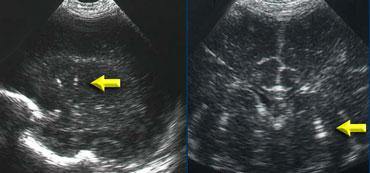

Xuất huyết nội sọ độ 2

Hình bên trái là xuất huyết nội sọ độ 2.

Trên mặt cắt đứng ngang, chỉ nhìn thấy khoang vách trong suốt.

Cả hai não thất bên đều chứa đầy máu, nhưng không có giãn não thất.

Hình bên trái là cùng bệnh nhân sau 3 ngày.

Các não thất giãn rộng và có hình ảnh hình thành cục máu đông.

Não úng thủy thứ phát xảy ra vài ngày sau xuất huyết độ 2 không nên bị nhầm lẫn với xuất huyết độ 3.